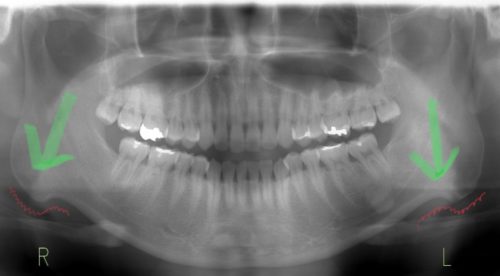

皆さんはこのようなレントゲンを撮ったことはありますか?

この部分の角度を見るだけで、肩こりしやすいかが分かる!

・・・とまでは残念ながら言えませんが、いわゆるエラと呼ばれる部分で、

このようにS字に曲がっている場合は、食いしばりの力が若干強めだと言われています

食いしばる力が強い、頻度が多いと、歯の痛み、特に奥歯の痛みにも関わってきます

奥歯が痛いけど虫歯じゃない、そんな時は、この食いしばりが原因のことが多いです

ちなみにこれは僕のレントゲンで

食いしばりが強く、奥歯に激痛が走ったことがありました

マウスピースを使用し、痛みは治まったので、現在はマウスピースを使用していません